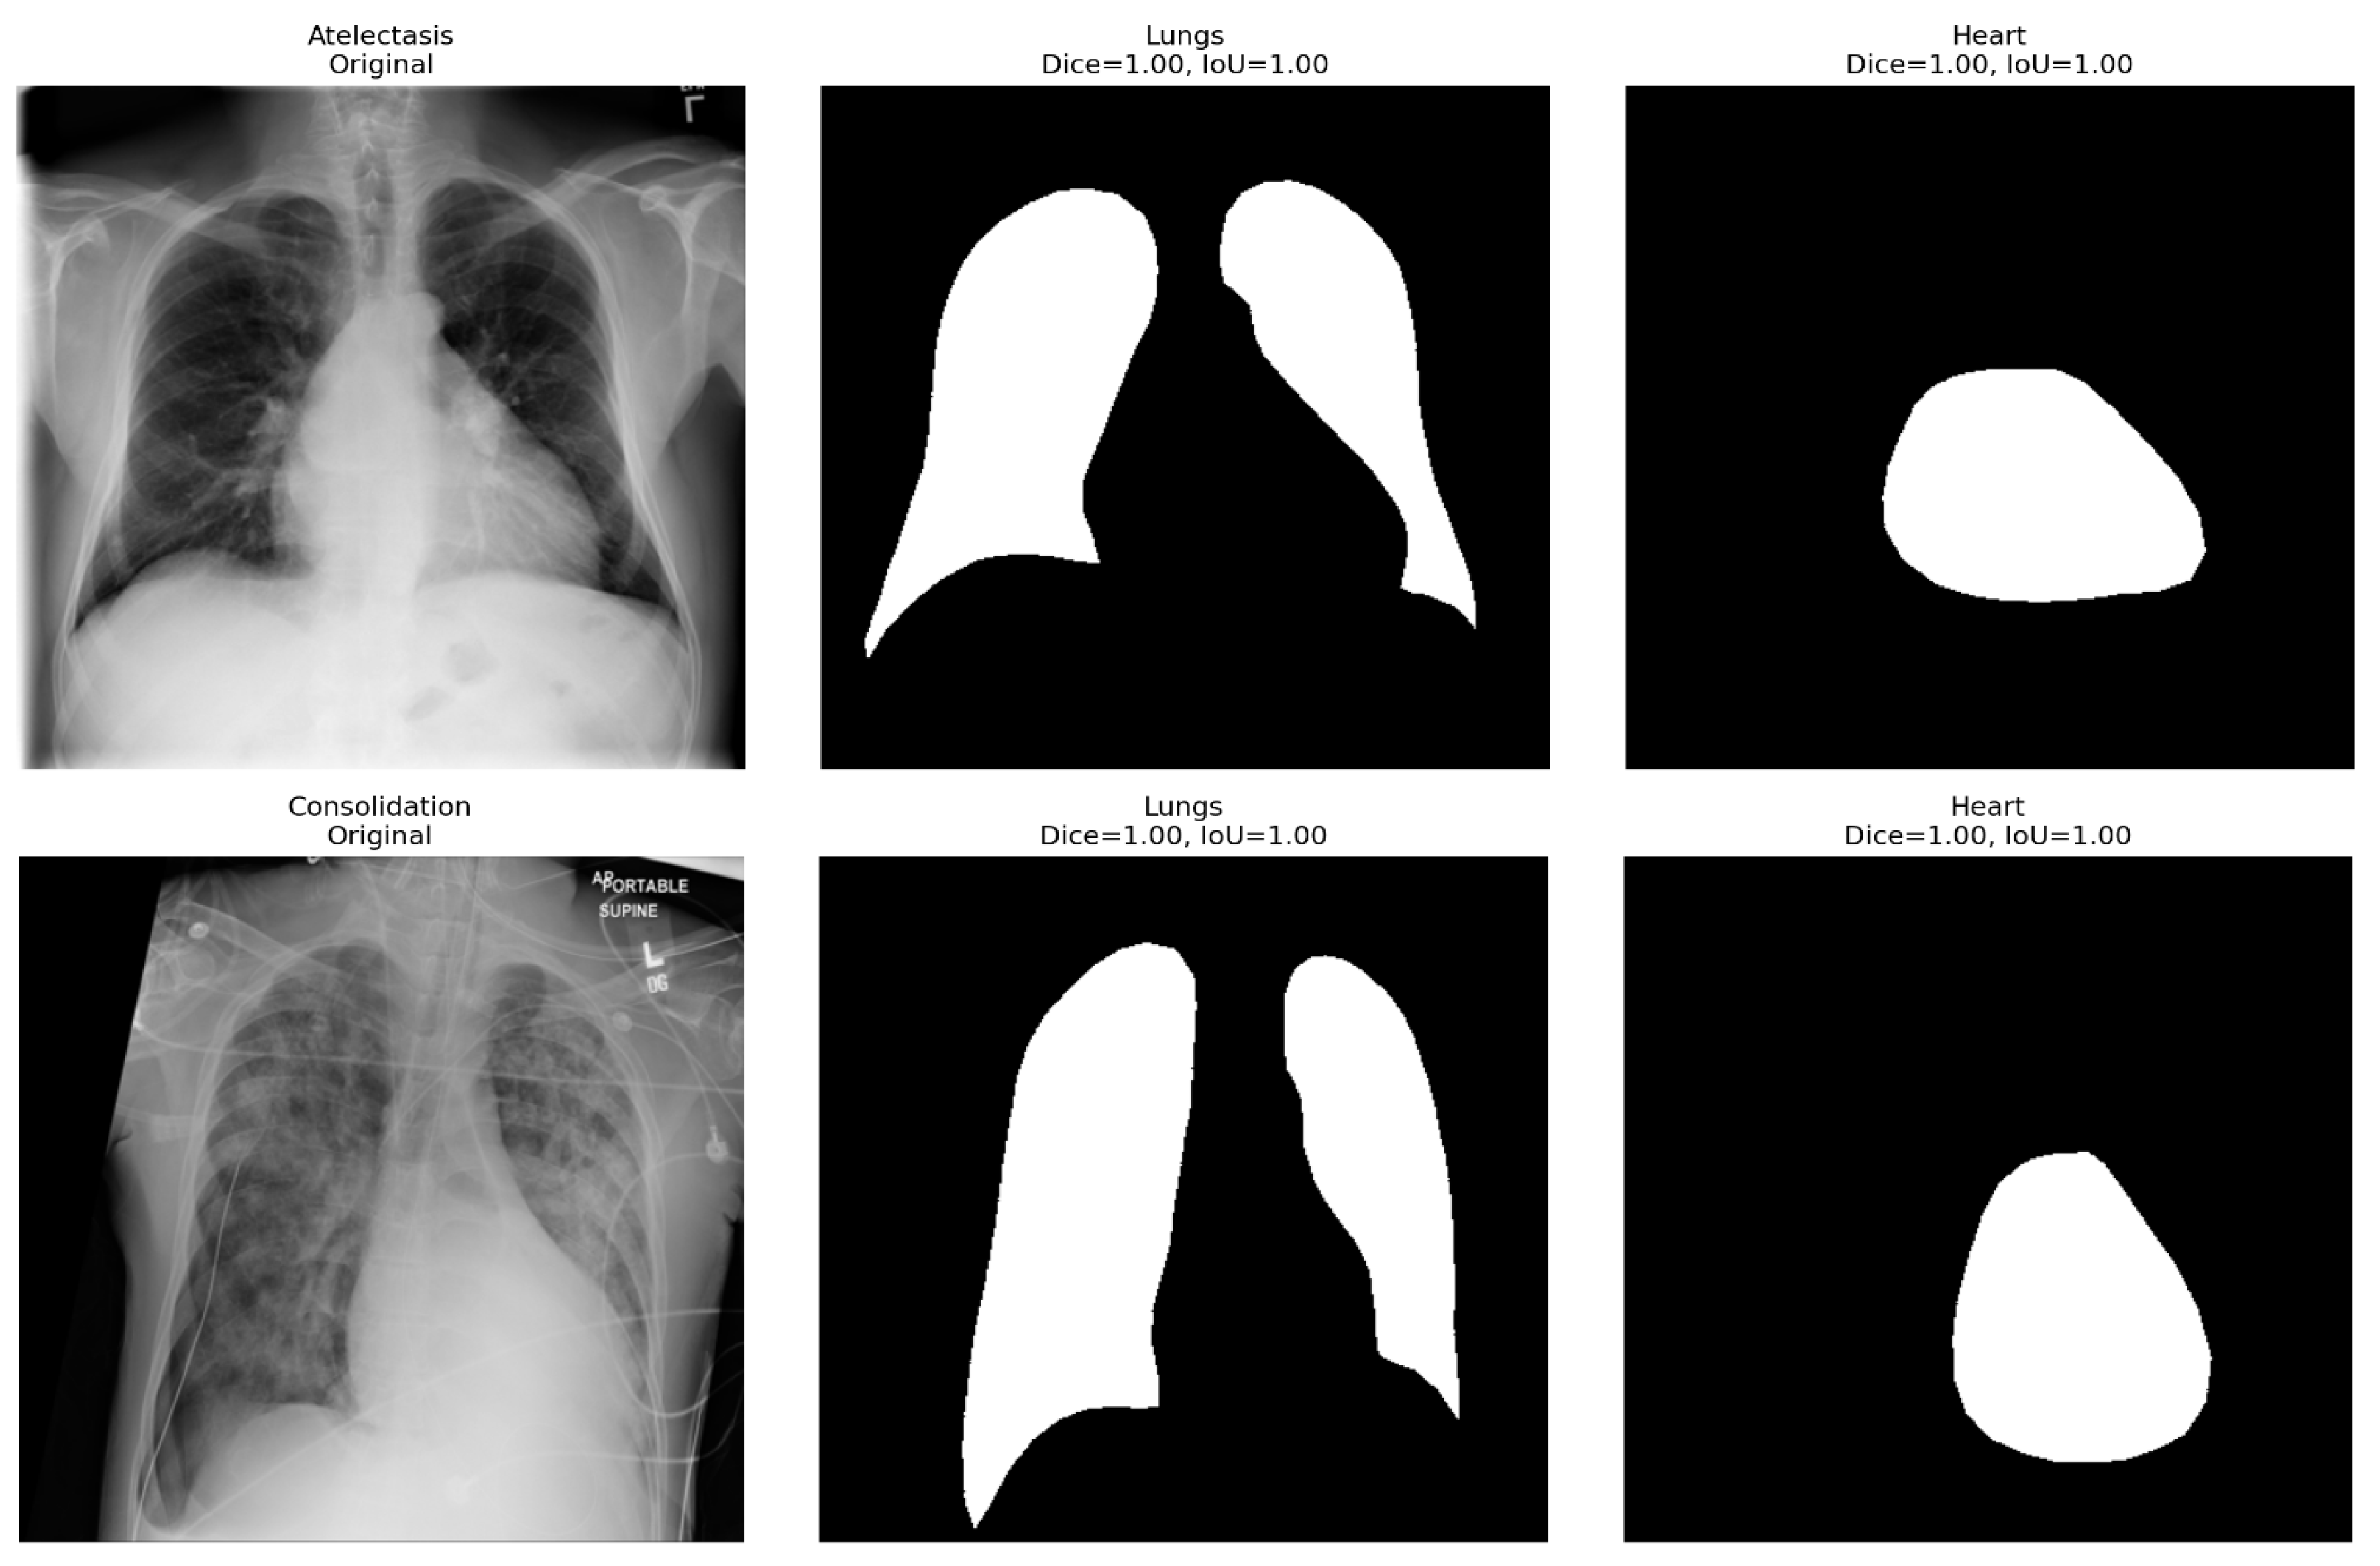

The introduction of anatomical supervision significantly improved the spatial localization and diagnostic accuracy of this hybrid model. The auxiliary segmentation branch, trained with Dice-based supervision using CheXmask anatomical masks, ensured that the feature extractor focused on physiologically significant lung and heart regions rather than spurious background information or textual artifacts.

The segmentation results achieved perfect scores, with the lung and heart regions achieving Dice coefficients and intersection-over-union (IoU) scores of 1.00, as shown in Figure 2. There was a perfect spatial overlap between the predicted masks and CheXMask ground truth, confirming that the anatomical supervision branch accurately mapped the organ boundaries with no leakage or omissions. Regardless of the numerous conditions processed by the segmentation framework, including cardiomegaly, consolidation, edema, and atelectasis, the masks retained sharp contours of the cardiac and pulmonary regions.

The addition of this supervision improved the global compatibility of the activation heatmaps and thoracic masks (more than 12) relative to the baseline hybrid setup. Mis-localization errors, previously observed as leakage of attention to the image corners or diaphragm margins, were significantly reduced. In particular, the effect was notable in diseases with a unique anatomical location, such as Pleural Effusion and Cardiomegaly, where class-specific Grad-CAM overlays already showed focal activation along the costophrenic angles and the cardiac silhouette, respectively. Such advances were reflected in the diagnostic gains in the per-class AUROC of effusion and emphysema, which increased from 0.82 to 0.89 and 0.90 to 0.95, respectively.